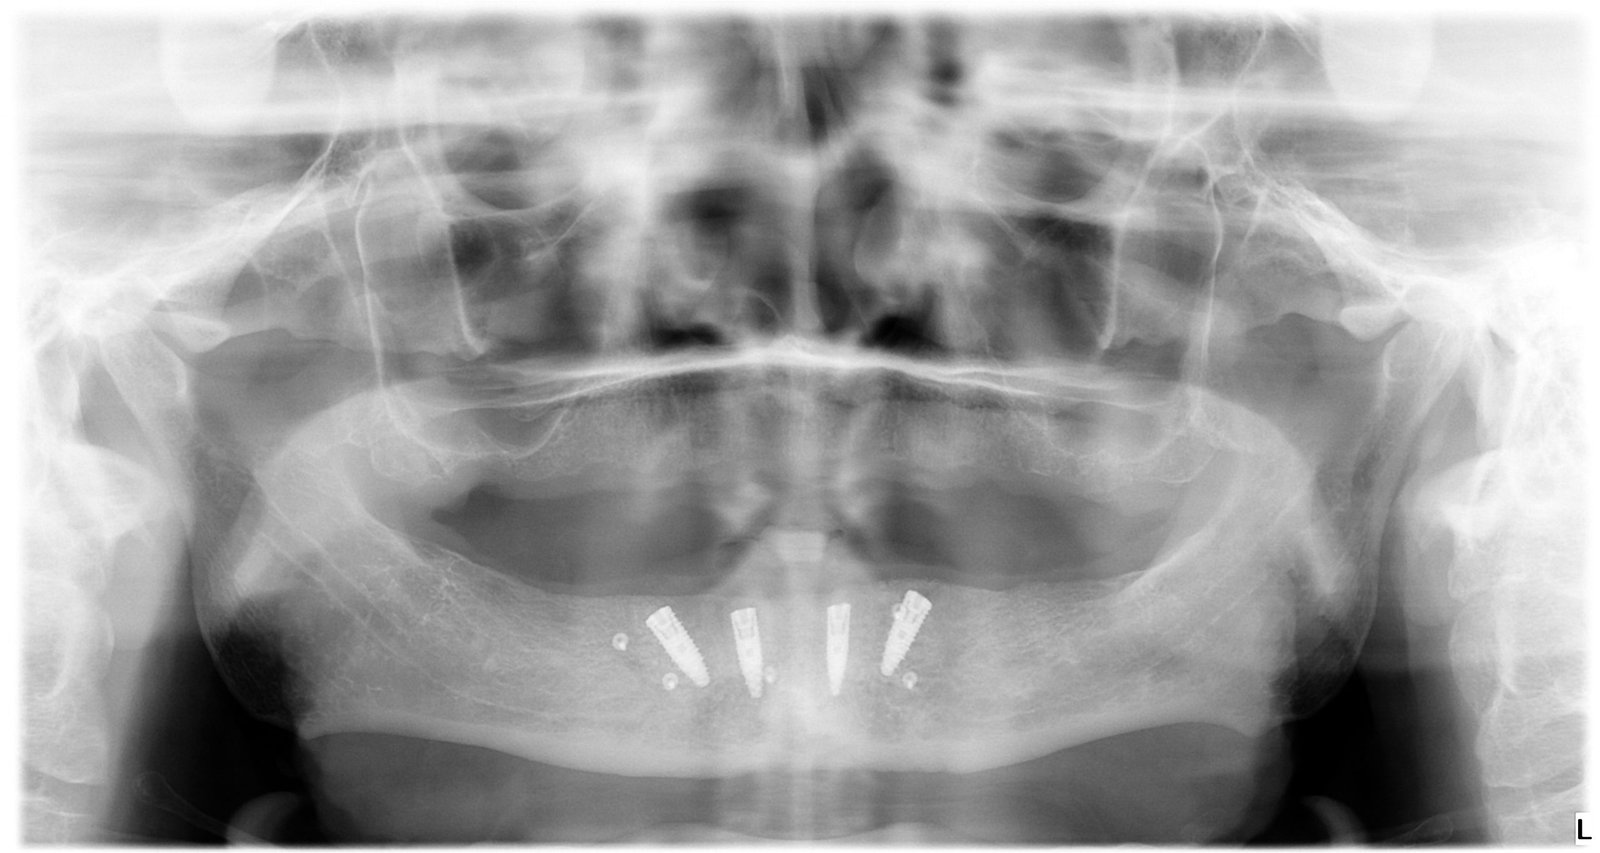

Caso 2 - caso de Implantes dentales

El paciente presentaba pérdidas dentales que comprometían tanto la función como la estabilidad de su mordida. Mediante un tratamiento con implantes personalizados logramos restablecer una dentadura fija, estable y adaptada a su anatomía.

Se observa la colocación de los implantes en la posición óptima, garantizando una base sólida para la posterior rehabilitación protésica.

La radiografía final confirma la correcta integración de los implantes, asegurando una solución duradera y completamente funcional.